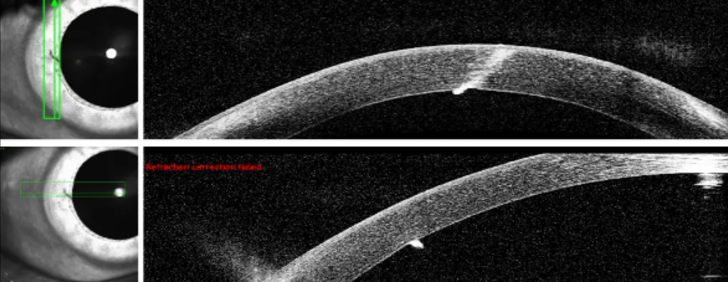

Doktorlar, şans eseri hastanın korneasını delmeyen ve körlüğe neden olabilecek kıymığı çıkarmadıklarını söyledi. Adama normal hayatına devam etmesini, herhangi bir ağrı ya da görme sorunu olması durumunda doktora başvurmasını söylediler.

Schepens Göz Araştırma Enstitüsü ve Harvard Üniversitesi'nden Dr. Asmaa Zidan The Post'a yaptığı açıklamasında, "Yabancı cisim, korneanın derinlerinde yer aldığı ve ön kamaraya ulaştığı için çıkarılmadı. Yine de yakın takip önerildi ve hastaya yeni semptomlar görülmesi halinde geri dönmesi tavsiye edildi. Bu gerçekten olağandışı ve istisnai bir durum" dedi.